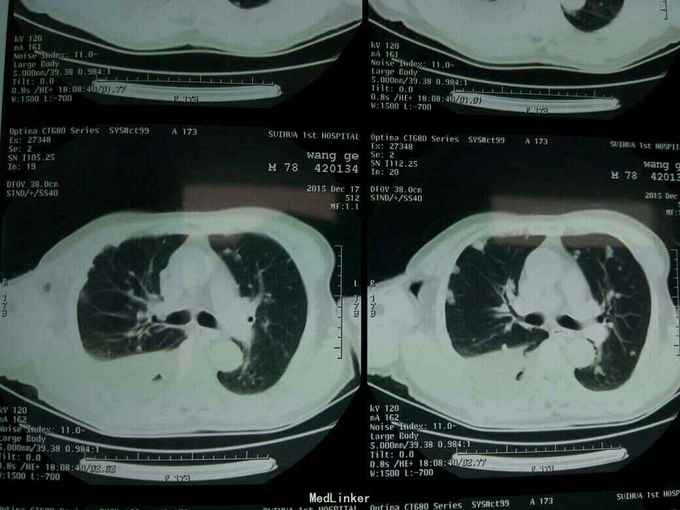

根据病史查体诊断:腰间盘突出症待确诊。应用消肿营养神经镇痛治疗。一天。查核磁共振示:腰椎多节段间盘突出伴椎管狭窄。第二腰椎骨破坏侵及椎板。部分突入椎管,脊髓受压。诊断:腰间盘突出伴椎管狭窄。第二腰椎转移癌,脊髓受压。经与家属沟通,查双肺CT:双肺下叶炎症。肺部纤维化。可见肿瘤阴影。肋骨及胸膜受累。胸椎部分骨破坏。最终诊断:双肺癌,胸椎,腰椎骨转移,脊髓受压。多节段腰椎间盘突出。病人至肿瘤科治疗。